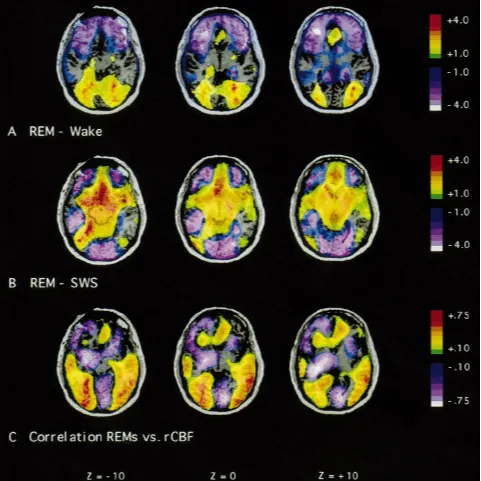

Challenge: Understanding seizure patterns during REM sleep is critical for developing therapies for patients with epilepsy, but brain connectivity is complex and hard to measure.

Mitacs’ Role: Funded applied research using high-density EEG and AI to map brain connectomes and identify seizure susceptibility during unstable REM sleep.